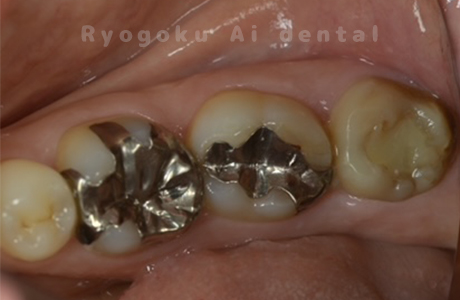

Case27

-

重度カリエス

歯牙移植咬合面術前 -

移植する親知らず

歯牙移植術直後咬合面

歯牙移植術後咬合面

- 原因

- 重度カリエス

- 治療内容

- 自家歯牙移植、部分矯正

- 治療費用

- 220,000円(移植費用)

110,000円(部分矯正費用)

虫歯が大きく、保存不可能となった歯を上の親知らずと交換する自家歯牙移植を行いました。移植歯が小ぶりであったため、部分矯正を行い問題なく噛み合い、経過良好です。

<リスク・副作用>

治療後、痛みや違和感、出血、腫れなどが出る事があります。喫煙者、糖尿病などの方の場合、歯が生着しない場合があります。